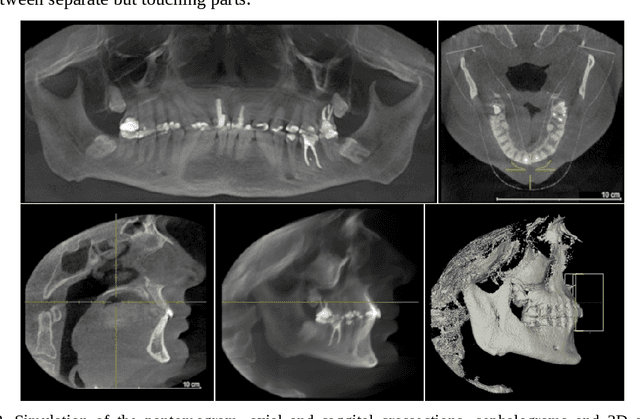

Abstract:The purpose of this chapter is to discuss methods of acquisition, visualization and analysis of the dynamics of a complex biomedical system, illustrated by the human stomatognathic system. The stomatognathic system consists of the teeth and the skull bones with the maxilla and the mandible. Its dynamics can be described by the change of mutual position of the lower/mandibular part versus the upper/maxillary one due to the physiological motion of opening, chewing and swallowing. In order to analyse the dynamics of the stomatognathic system its morphology and motion has to be digitized, which is done using static and dynamic multimodal imagery like CBCT and 3D scans data and temporal measurements of motion. The integration of multimodal data incorporates different direct and indirect methods of registration - aligning of all the data in the same coordinate system. The integrated sets of data form 4D multimodal data which can be further visualized, modeled, and subjected to multivariate time series analysis. Example results are shown. Although there is no direct method of imaging the TMJ motion, the integration of multimodal data forms an adequate tool. As medical imaging becomes ever more diverse and ever more accessible, organizing the imagery and measurements into unified, comprehensive records can deliver to the doctor the most information in the most accessible form, creating a new quality in data simulation, analysis and interpretation.